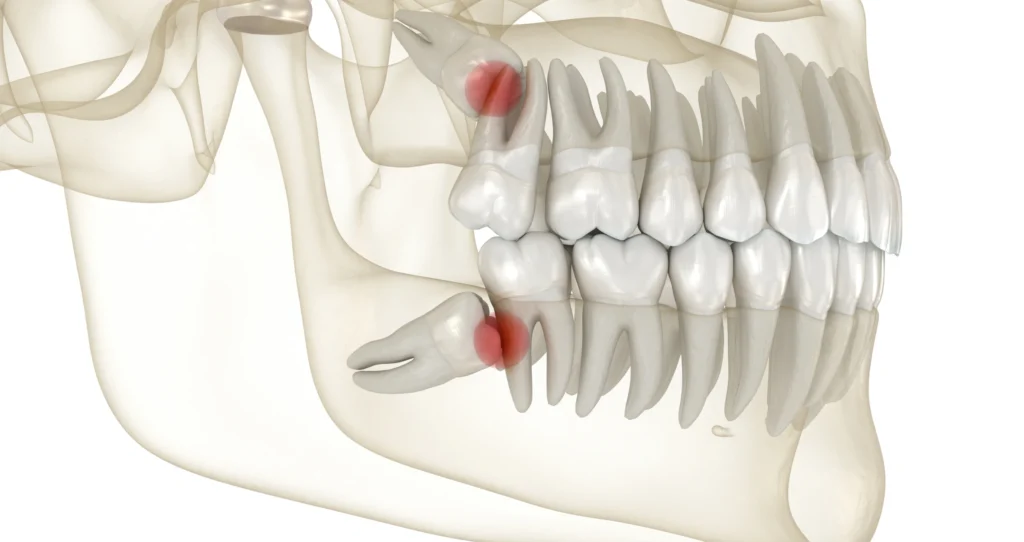

Chirurgie orale

Conseils pré-opératoires

Chirurgie orale

Conseils post-opératoires